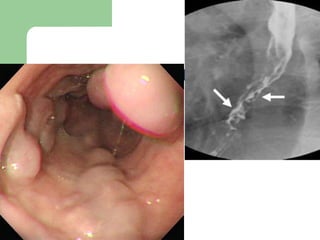

Peptic ulcer Most common cause of upper GI bleed 1/2- 2/3. Causes:H. pylori 40-50%,NSAID’s 40-50% andOther (Z-E syndrome)   Duodenal bleed is  four times  more common than gastric ulcer bleed.  Duodenal ulcers are usually  posterior  and involve branches of the gastroduodenal artery. Benign gastric ulcers bleed more than malignant ulcers. There will be  significant bleeding in 10-15% surgical intervention is needed in 20%

Duodenal ulcers located on the  anterior  wall are prone to  perforation  and present as peritonitis and free air.  Those on the  posterior  wall, which is the more common location, lead to  bleeding  The gastroduodenal artery

Peptic ulcer Mostcommon cause of upper GI bleed 1/2- 2/3. Causes:H. pylori 40-50%,NSAID’s 40-50% andOther (Z-E syndrome) Duodenal bleed is four times more common than gastric ulcer bleed. Duodenal ulcers are usually posterior and involve branches of the gastroduodenal artery. Benign gastric ulcers bleed more than malignant ulcers. There will be significant bleeding in 10-15% surgical intervention is needed in 20%

Duodenal ulcers locatedon the anterior wall are prone to perforation and present as peritonitis and free air. Those on the posterior wall, which is the more common location, lead to bleeding The gastroduodenal artery